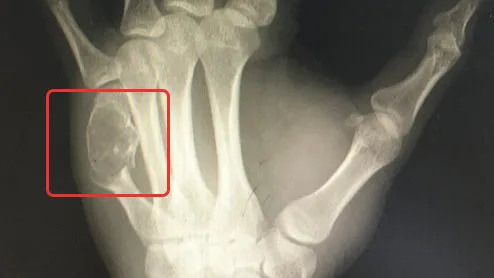

医生告诉他这不是一般的键盘手了 , 手上肿起来的大包里面已经长了骨肿瘤 , 而且这个瘤把里面正常的骨头“融”成豆腐渣了.......

期间 , 他的左手症状时好时坏 , 只是慢慢鼓起了个包 , 但也没多大碍 。 直到不小心磕到桌子 , 手指严重到不能动了 , 他才找上医生 , 这也才有了开头的新闻 。